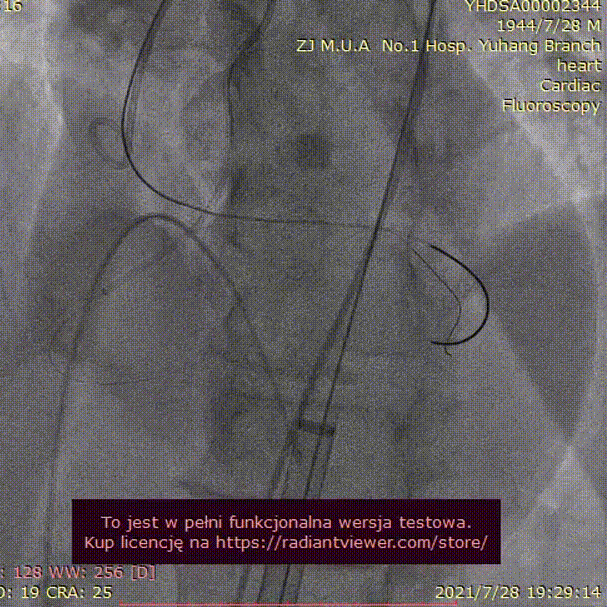

手术过程:

23mm球囊预扩

(有腰征,无瓣周漏,右冠开口阻塞)

TAV24 瓣膜释放前定位

释放4.0*30mm烟囱支架

植入后造影

术后压差1mmHg